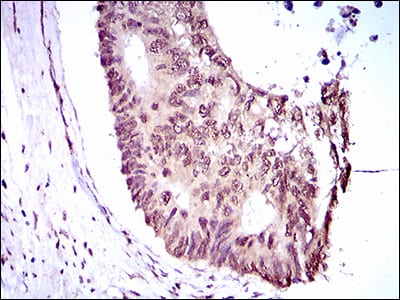

分类: 科研抗体货号: 30507别名: FLK2; STK1; CD135; FLK-2应用: IHC反应种属: Human